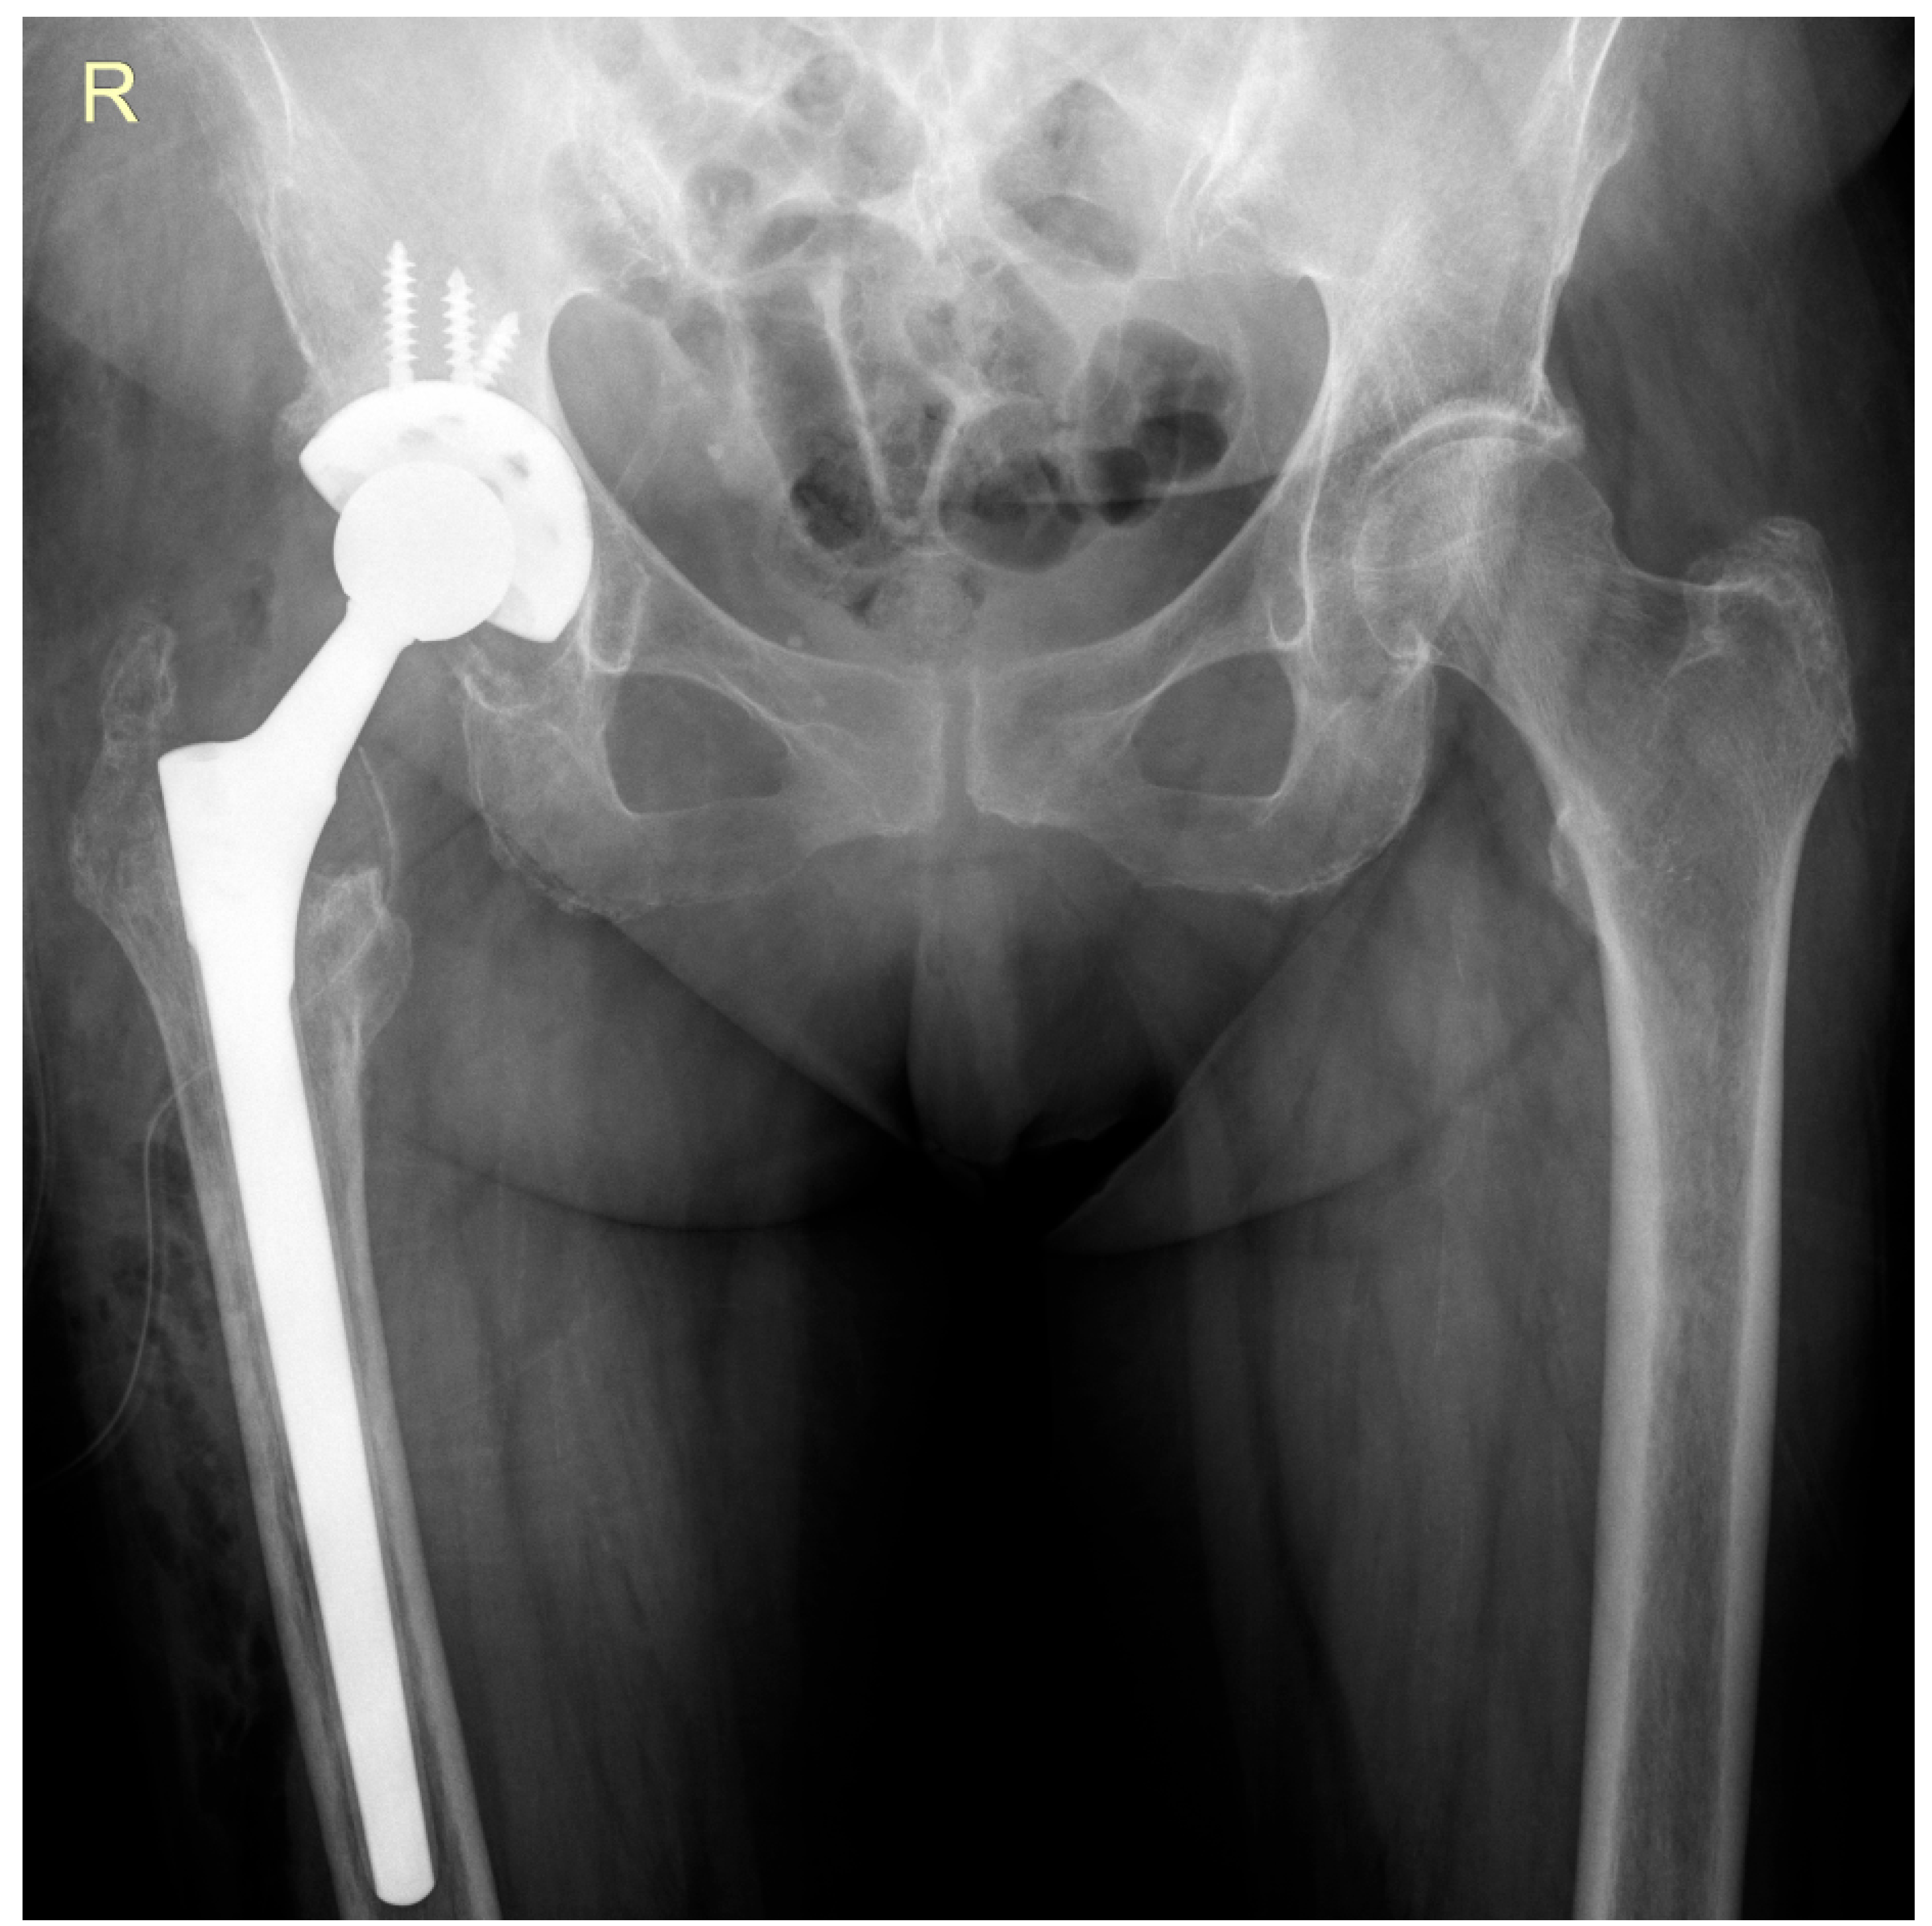

2. Case Report